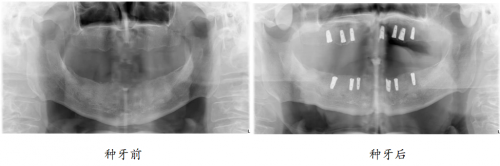

“口福行动”让80岁高龄老人缺牙重生

82岁的孙爷爷,10年前就已全口无牙,一直戴着活动假牙勉强吃饭。

近3年,活动假牙松动厉害,一吃东西就脱落,孙爷爷只能喝打成糊状的蔬菜和肉,“我看到这些,一点胃口都没有,肚子还空着,嘴里又吃不下,不知道是饿还是饱。总之吃饭好似‘上刑场’一样。”牙齿的缺失,让孙爷爷无比怀念老伴做的红烧肉,渴望重新拥有一口健全、有强劲咀嚼力的好牙,回到可以开怀大笑的日子。

如今种牙1年后,孙叔叔的生活质量得到改善,一日三餐饮食结构丰富,红烧肉、苹果、坚果样样都能轻松消化,“多亏在‘修复失牙·口福行动’公益活动上遇见綦健院长,我现在精气神十足,邻居都说我年轻了10岁。”重获新牙的孙爷爷高兴道。